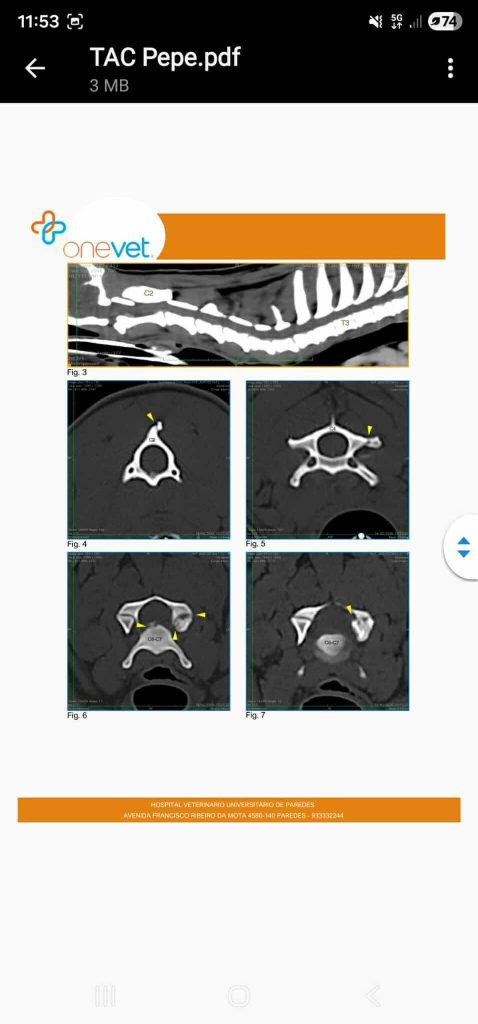

Der Rüde hat ein Handicap, er läuft linksseitig krumm und stolpert. Wir haben Pepe gründlich untersucht und mit trauriger Wahrscheinlichkeit hat sich bestätigt… er muss einen Schlag auf die Halswirbelsäule und den Kopf bekommen haben… Es ist nichts tumoröses und es ist nicht behandelbar, sondern sein Handicap.Pepe ist ein besonderer Hund, der besondere Menschen braucht, die ihn so lieben wie er ist. Er ist fröhlich, verschmust und etwas wackelig auf den Beinen.